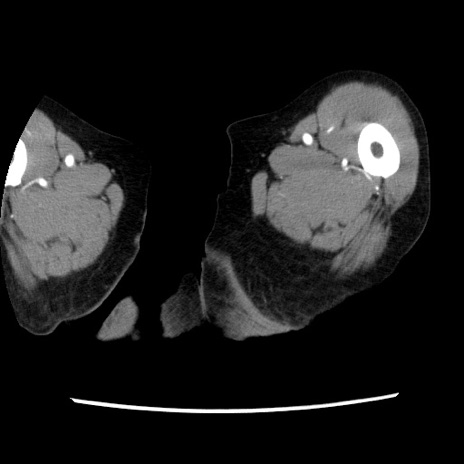

冠状断像